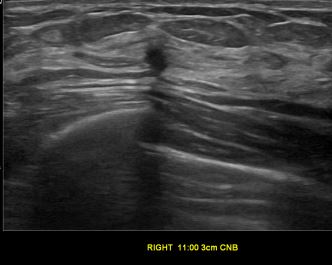

상기환자는 외부 건강검진 이상소견으로  정밀검사위해 내원하신 60대 중반

여성분으로 의심스러운 우측유방혹 조직검사 시행해 유방암으로 진단되었습니다